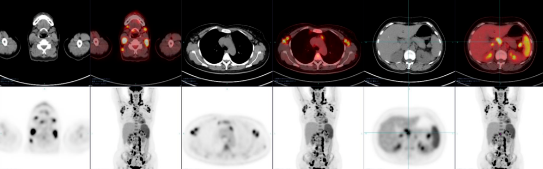

Fig.1 PET/CT、PET与MRI异机融合

左侧颈静脉鞘区囊实性病变 ,壁厚薄稍不均匀,CT均值约20Hu,大小约21mm×16mm,放射性摄取不均匀增高,SUVmax3.8。MRI呈明显长T2信号,壁稍不规则。双侧颌下及颈静脉区另见多个肿大淋巴结,密度均匀,呈长T2信号,放射性摄取不同程度增高,SUVmax5.8。

Fig.2 PET/CT、MRI平扫及DWI

左侧颈静脉上区囊实性病灶, 呈稍长T1稍长T2信号,信号不 均,中央囊变,DWI(b=800) 呈高信号,中央ADC值增高,囊壁稍不规则,ADC值约 0.872×10-3。

左侧颈部颈静脉鞘区结节影,密度不均匀,边缘见壳状及斑点状钙化,呈长T2信号,信号稍不均匀,放射性摄取增高,SUVmax3.6。

左侧上纵隔淋巴结肿大,边缘见点状钙化,放射摄取增高,SUVmax3.8; 左侧锁骨上窝结节状钙化,放射性摄取未见异常增高。

Fig.5 PET/CT、PET与MRI

异机融合双侧扁桃体肿大,未见明显异常密度影, T2WI扁桃体信号均匀,未见异常信号,放射性摄取明显增高,SUVmax14.5。

双侧甲状腺肿大,密度弥漫减低,CT值约60Hu,放射性摄取弥漫增高,SUVmax5.7。

MRI与PET异机融合

甲状腺肿大,呈稍长T2信号,信号稍不均匀,左叶见结节状长T2信号,放射性摄取弥漫增高,SUVmax5.7。